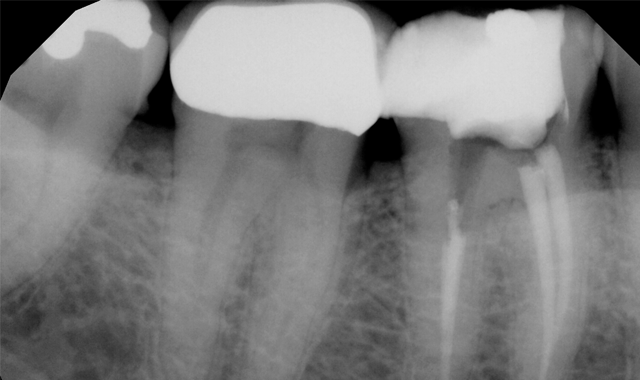

The patient was referred for root canal therapy and after three weeks returned for a restoration (Fig. 2). The tooth was cleaned of temporary restorative material and was prepared for a post and core. A Dentatus Classic Surtex® (Dentatus) metal post was cemented with self-adhesive resin cement (TotalCem, Itena) and an adhesive layer of CLEARFIL SE Bond (Kuraray Dental) was placed as per manufacturer’s instructions, followed by light curing for 10 seconds.

Fig. 2 Fig. 3

The chamber was then filled using CompCore™ AF (Premier Dental). CompCore AF is a dual-cured, fluoride-releasing, radiopaque composite core buildup indicated for vital and nonvital teeth (Figs. 3-4).